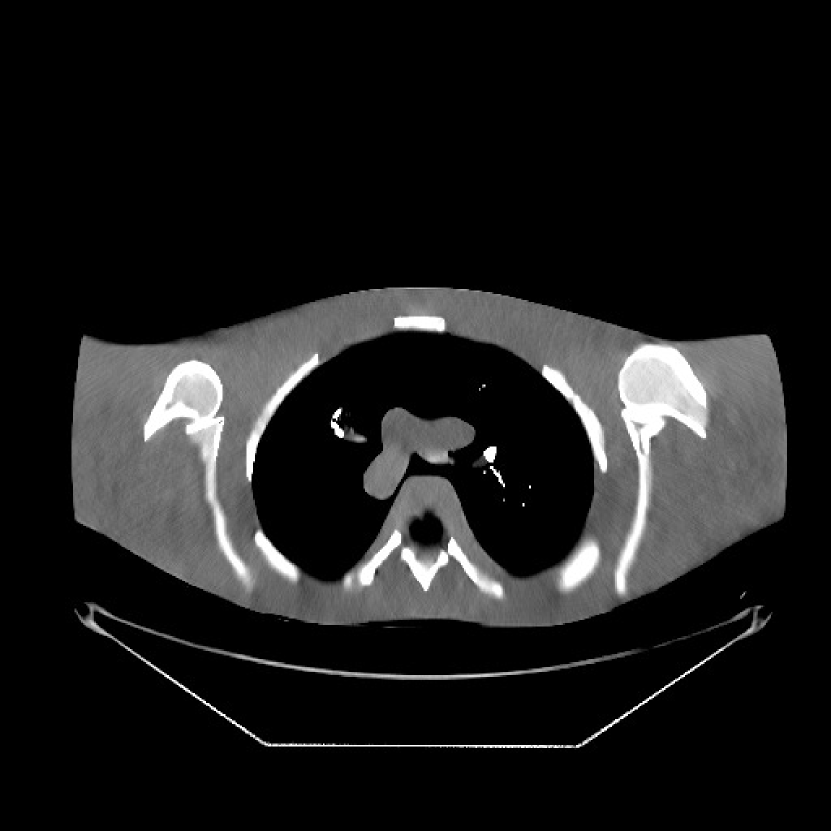

Refer to caption

Figure 1: Reconstruction targeted ROI of the true XCAT phantom displayed with central slices along the axial, sagittal and coronal directions. The display window is [800, 1200] HU.

We simulated 3D axial cone-beam scans using a 840×840×9684084096840\times 840\times 96 XCAT phantom with Δx=Δy=0.4883subscriptΔ𝑥subscriptΔ𝑦0.4883\Delta_{x}=\Delta_{y}=0.4883 mm and Δz=0.625subscriptΔ𝑧0.625\Delta_{z}=0.625 mm. We generated sinograms of size 888×64×98488864984888\times 64\times 984 using GE LightSpeed cone-beam geometry corresponding to a mono-energetic source with I0=1×104subscript𝐼01superscript104I_{0}={\color[rgb]{0,0,0}1\times}10^{4}, 5×1035superscript1035\times 10^{3}, 3×1033superscript1033\times 10^{3}, and 2×1032superscript103{2\times 10^{3}} incident photons per ray and no scatter, respectively. Tab. I shows percentages of non-positive measurements under different dose levels. We set these non-positive measurements to 1×1051superscript1051\times 10^{-5} for generating the post-log sinogram that PWLS-based methods rely on [13]. We reconstructed the 3D volume with a size of 420×420×9642042096420\times 420\times 96 at a coarser resolution of Δx=Δy=0.9766subscriptΔ𝑥subscriptΔ𝑦0.9766\Delta_{x}=\Delta_{y}=0.9766 mm and Δz=0.625subscriptΔ𝑧0.625\Delta_{z}=0.625 mm. The patch size during reconstruction was 8×8×88888\times 8\times 8 and the stride was 3×3×33333\times 3\times 3. For evaluating reconstruction performance, we chose an ROI that was composed of the central 64 out of 96 axial slices, and refer to it as the reconstruction targeted ROI. Fig. 1 shows the central slices of the true XCAT phantom inside this ROI along three directions. In the reconstruction stage of PWLS-ULTRA and SPULTRA, we used 4 iterations for the image update step, i.e., P=4𝑃4P=4, for a good trade-off between algorithms’ convergence and computational costs. We used 121212 ordered subsets, i.e., M=12𝑀12M=12, to speed up the algorithm. The initial image for the ULTRA methods was reconstructed by PWLS-EP, whose regularization parameter was set empirically to ensure good reconstruction quality as βep=213subscript𝛽𝑒𝑝superscript213\beta_{ep}=2^{13} for all the experimented dose cases. We used an analytical filtered back-projection (FBP) method FDK [59] to initialize PWLS-EP. The FDK images of XCAT phantom for all the dose levels are shown in the supplement. Due to the fact that SPULTRA has a similar cost function as PWLS-ULTRA in each outer iteration, we used the same parameter settings for both methods: β=4×104𝛽4superscript104\beta=4\times 10^{4} and γc=4×104subscript𝛾𝑐4superscript104\gamma_{c}=4\times 10^{-4}, which we observed worked well for all the dose levels we tested.